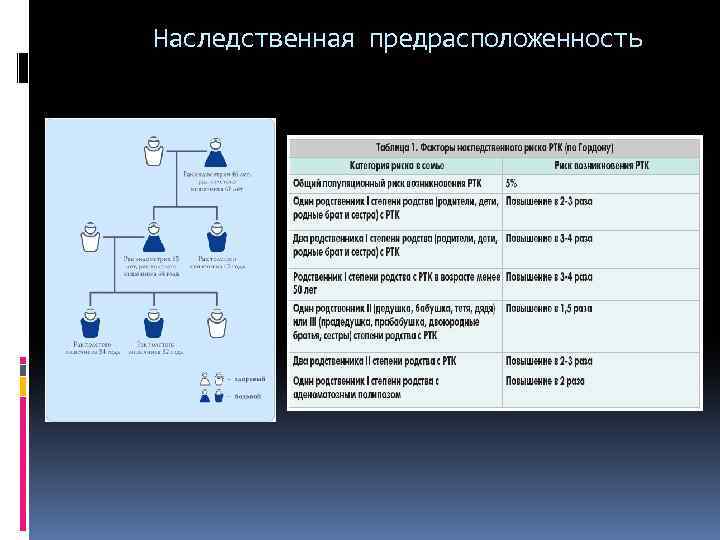

Наследственная предрасположенность